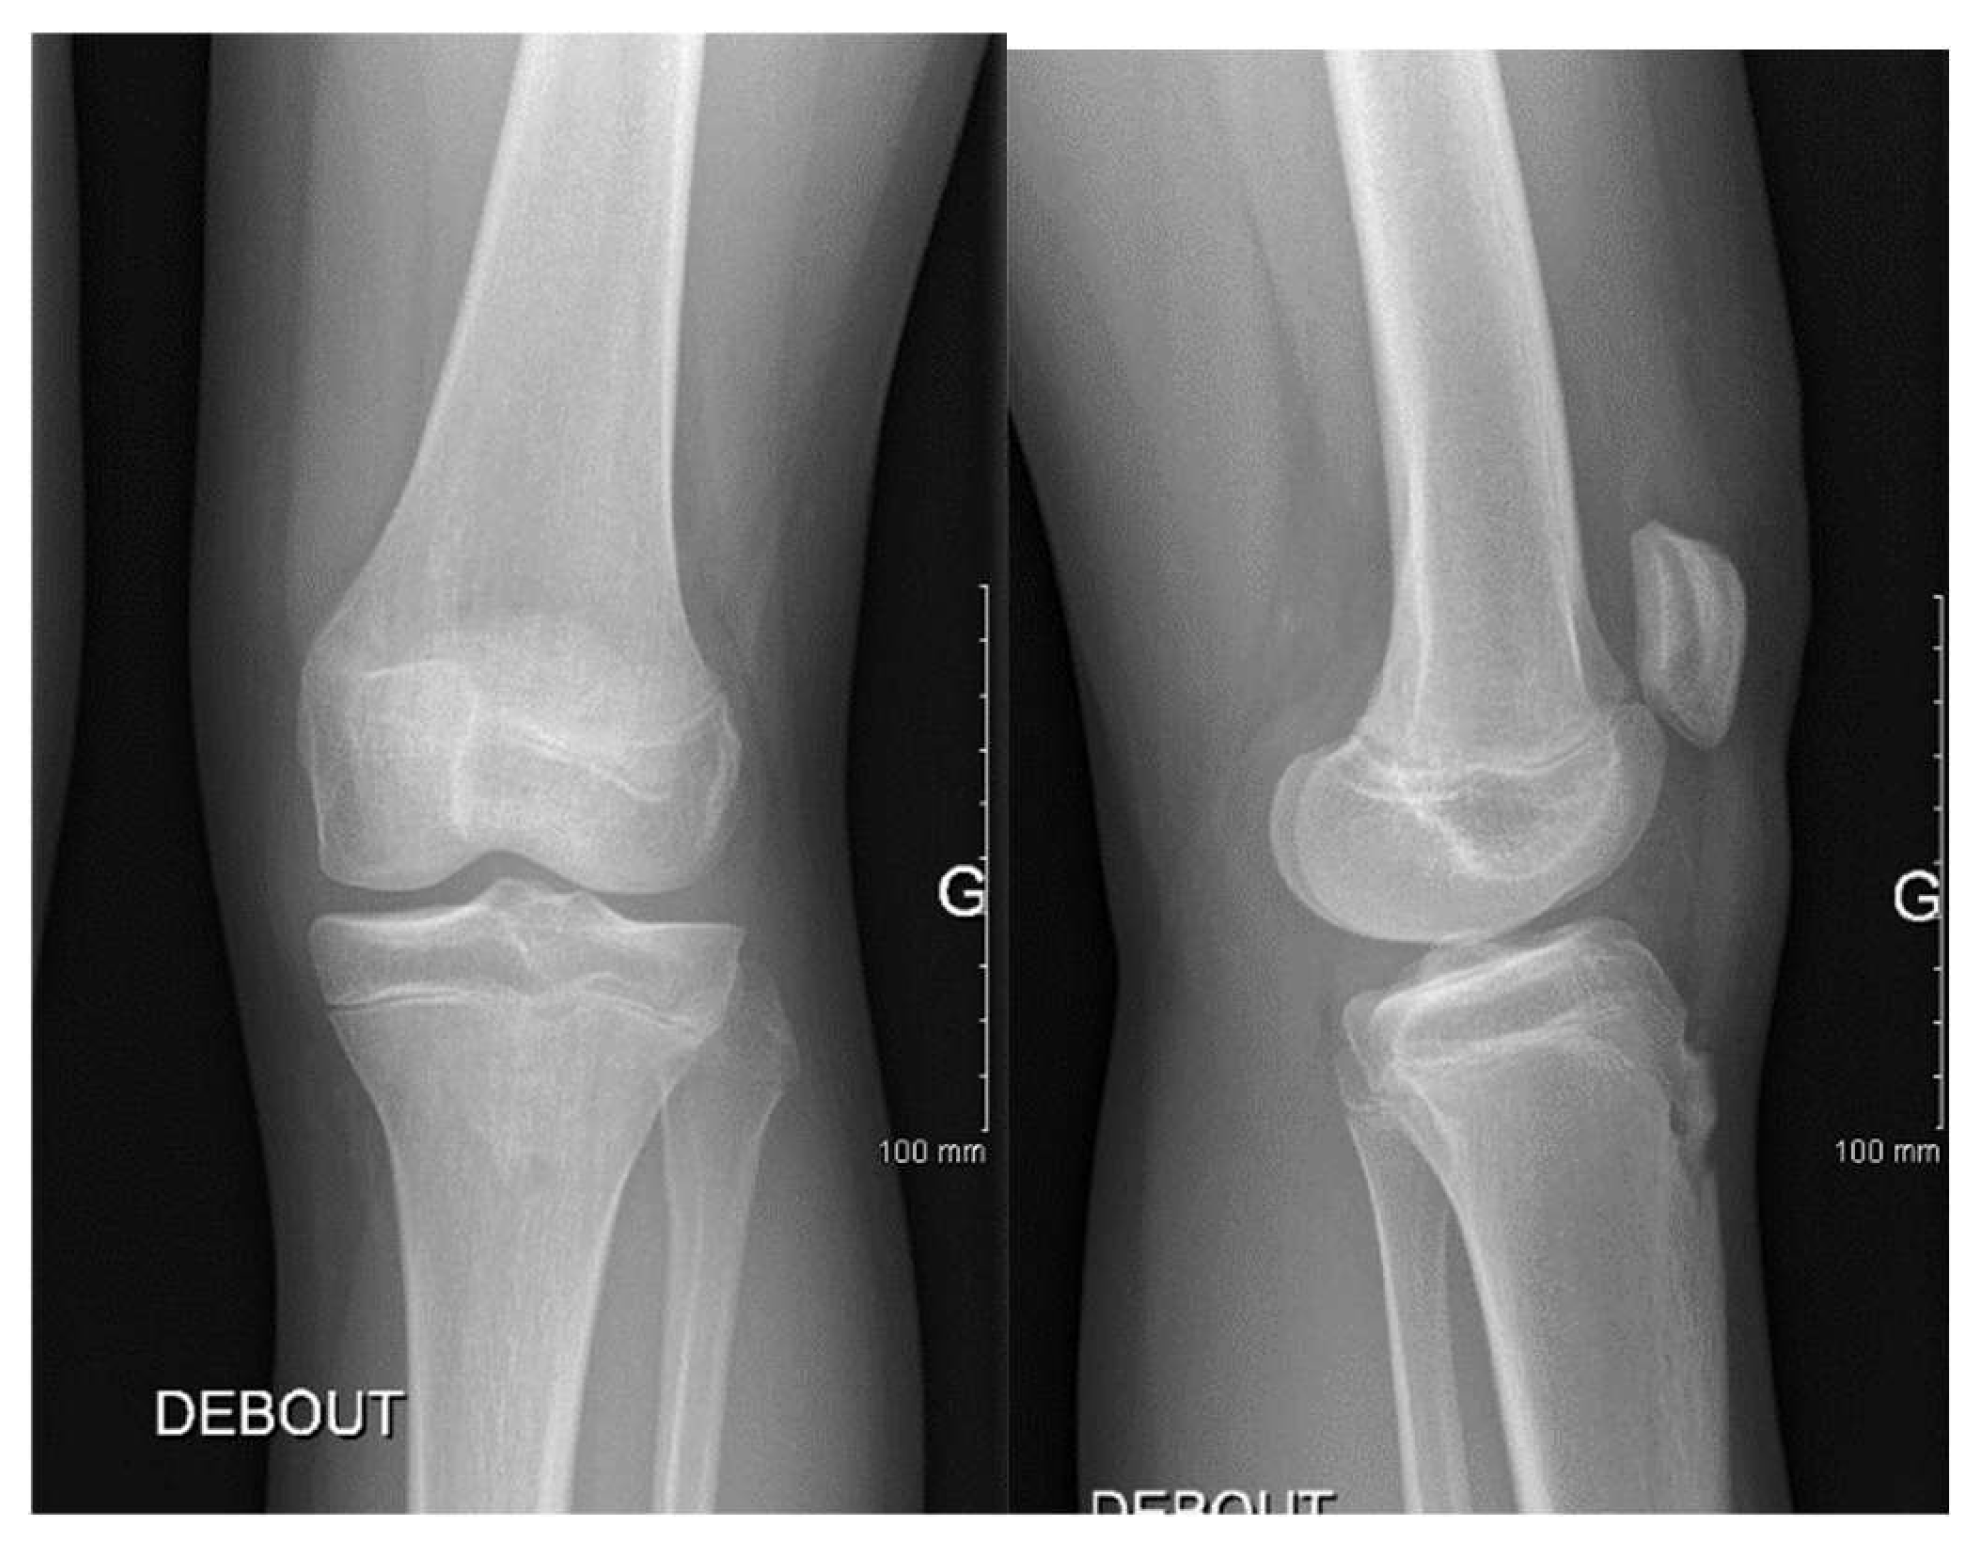

3.1. Case 1—P.E.

3.2. Case 2—S.C.S.

3.3. Case 3—G.L.

| P.E. | 12 | Bilateral (symptomatic right) | Chronic pain, effusion, normal ROM | None | 3 surgeries: partial meniscectomy (12 years), suture for horizontal tear (13 years), suture for radial tear (14 years) | 1 year after third surgery: symptom-free, resumed school sports |

| S.C.S. | 13 | Left | Pain, occasional locking, normal ROM | Dancing | 1 surgery: partial meniscectomy and suture for horizontal tear (13) | 6 months: symptom-free, full ROM, resumed dancing |

| G.L. | 14 | Bilateral (symptomatic right) | Pain, medial tenderness, normal ROM | Basketball | 1 surgery: partial meniscectomy and suture for horizontal tear (14) | 6 months: symptom-free, full ROM |